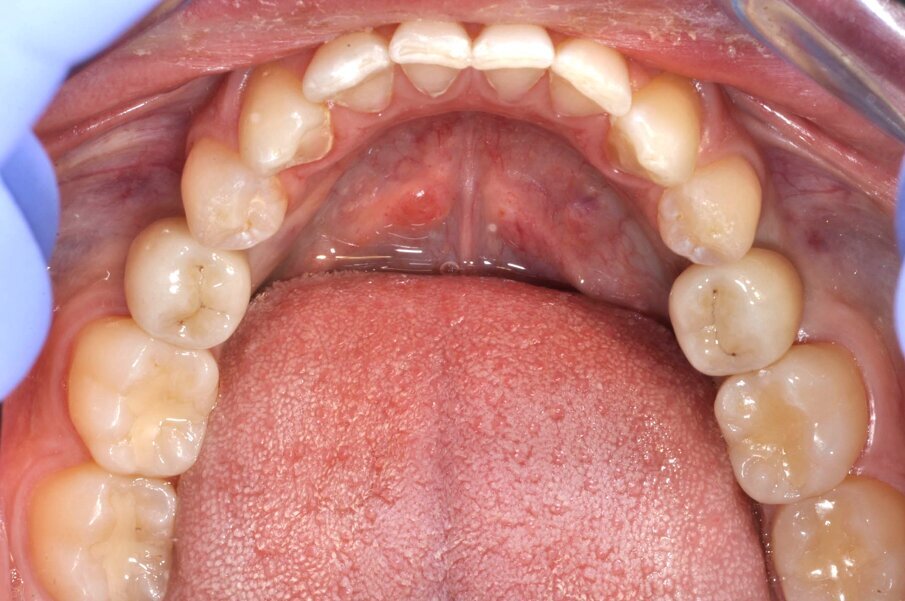

Fig. 1_In evidenza la persistenza dei decidui in quadrante 3-4.

Fig. 2_Visualizzazione occlusale sx.

Fig. 3_Visualizzazione occlusale dx.

Fig. 4_L’arcata inferiore.